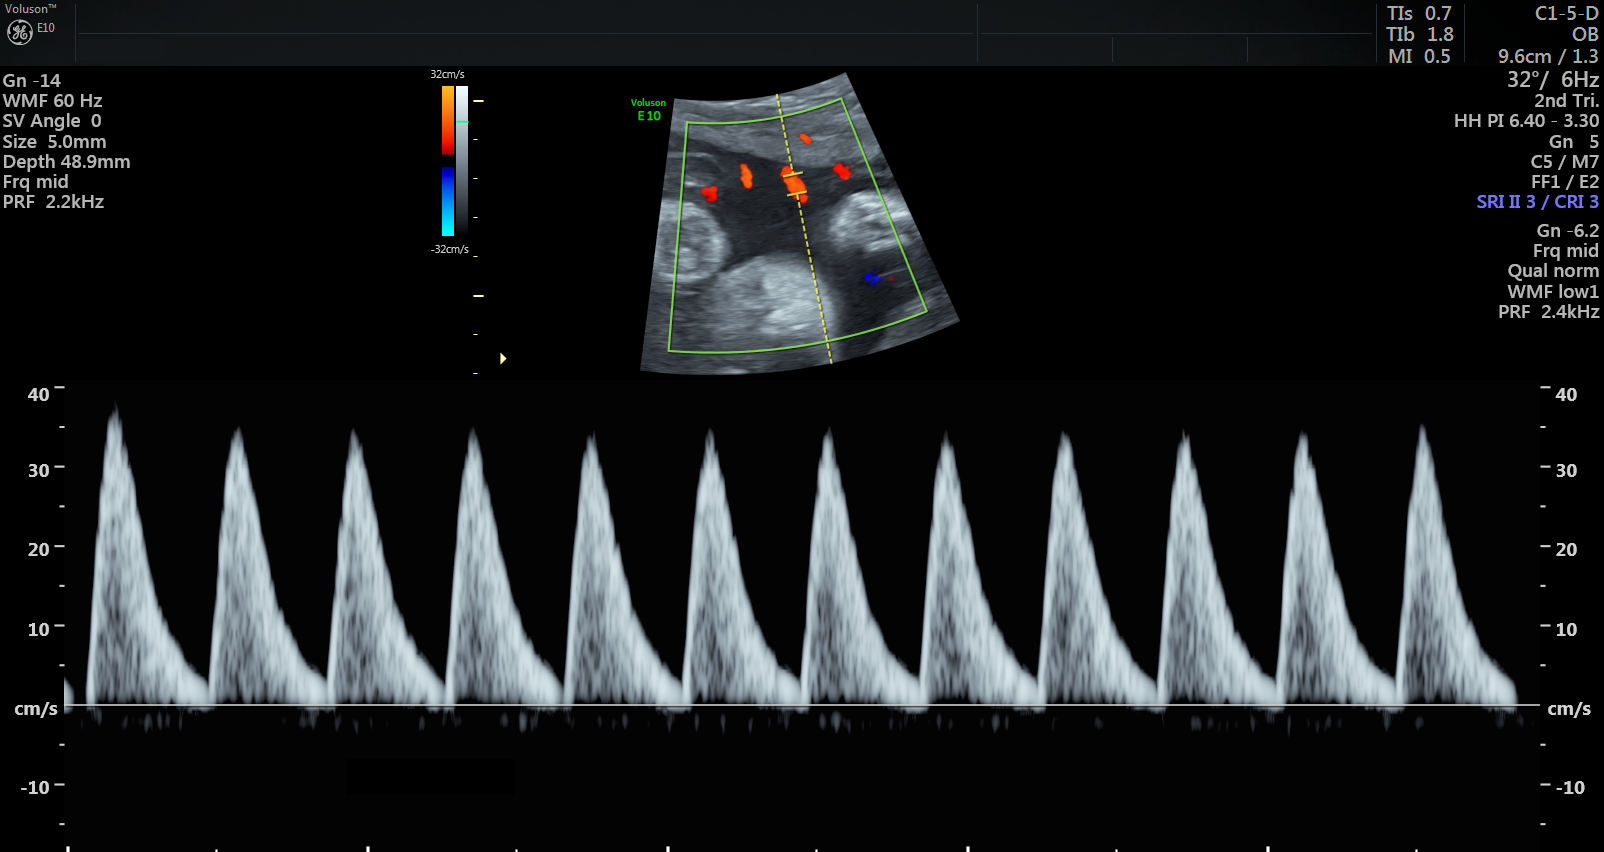

Currently, standard-of-care ultrasound scans measure blood flow at one point in the umbilical cord. The technique developed by Sled and his collaborators takes two measurements – one at the fetal end of the umbilical cord and one at the placental end. Sled says recording both measurements gives a much more accurate picture of the way blood is travelling through the umbilical cord.

“By looking at both measurements and the physics of how blood travels, we can get insight into how some of the finest blood vessels in the placenta are organized. The information this can provide to physicians is invaluable,” says Sled, who is also the Director of the Mouse Imaging Centre and a Professor and Vice-Chair in the Department of Medical Biophysics at the University of Toronto.

Animation showing where the new ultrasound technique measures blood flow along the umbilical cord. One measurement is taken at the fetal end and one is taken at the placental end.